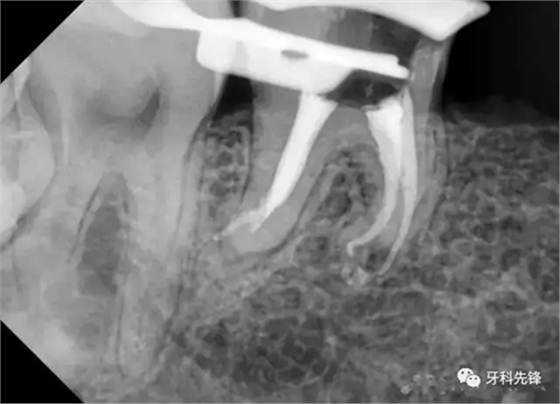

處置: 46右下牙槽神經(jīng)阻滯麻醉,46橡皮障隔濕,去凈腐質,開髓,拔髓,GG鉆擴大根管口,根管疏通,根測,ML=19.5mm,MB=18mm,DB=DL=18mm,EDTA作用下M2鎳鈦機擴至25#,試尖拍片,干燥根管,AHplus糊劑+牙塞尖+熱牙膠加壓根充,,聚羧酸鋅墊底,Z350納米樹脂充填,調合,拋光。

如果沒有橡皮障和MTwo,很難完成這個病例。